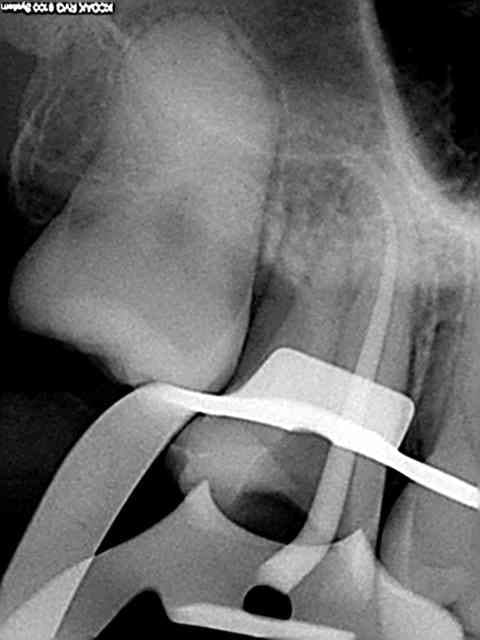

Faudrait que je la retrouve mais y'a une vidéo avec une radio qui m'a fait mal dans mon ego...

Sinon, pour répondre à la question, j'utilise un seul cône calibré Protaper, je descend avec le MacSpadden jusqu'à 5mm de l'apex sur CA bleu plein pot et ça tasse en 5 secondes (pas plus longtemps sinon ça chauffe, pas plus bas sinon ça fuse). Les astuces: un coup d'air pour dégager l'excès de ciment à l'entrée du canal avant introduction de l'instrument (le ciment fait tampon à la chaleur et gêne la fusion du cône), si ça ne suffit pas --> instrument de plus gros diamètre (il existe des sets pas chers avec des diamètres jusque 80, ça dépanne parfois sur un gros canal palatin ou après une dépose de tenon).